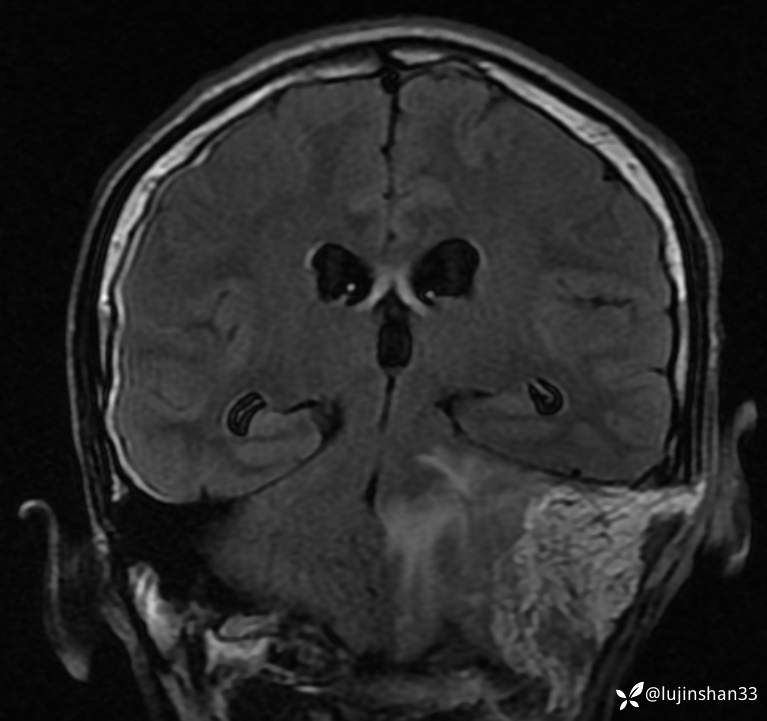

首次术前MRI

未行手术,4个月后复查,病变进展